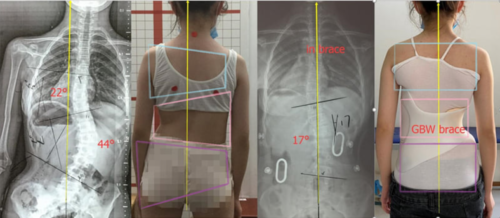

تشير الدراسات الطبية إلى أن الأطفال في سن 11 إلى 15 عامًا هم الأكثر عرضة لخطورة تطور الانحناء. والسبب هو أن هذه المرحلة تمثل فترة البلوغ والنمو السريع، حيث يزداد طول الطفل بشكل ملحوظ خلال وقت قصير.

التدخل المبكر بالعلاج مثل الأحزمة الحديثة PioBrace يمكن أن يوقف أو يصحح الانحناء.

عند الأطفال والمراهقين: الخطر الأكبر هو سرعة تطور الانحناء مع النمو. فمثلاً، إذا تجاوز الانحناء 30 درجة قبل سن 10 سنوات، فإن احتمالية التفاقم تصل إلى 100% إذا لم يتم التدخل. هذا قد يؤدي في النهاية إلى الحاجة لجراحة أو ظهور تشوهات واضحة.

العلاجات غير الجراحية مثل الأحزمة الحديثة PioBrace أثبتت فعاليتها الكبيرة في هذا العمر.

متى يحتاج الطفل المصاب باعوجاج العمود الفقري إلى علاج؟

إذا كان الانحناء بسيطًا، قد يكتفي الطبيب بالمتابعة الدورية.

إذا كان الانحناء متوسطًا، قد يوصى باستخدام الحزام الطبي PioBrace الذي يساعد في تصحيح الانحناء ومنع تطوره.

أكثر الأعمار خطورة للإصابة بالجنف هي من 11 إلى 15 عامًا، حيث يحدث النمو السريع وقد يتطور الانحناء بسرعة.

الأطفال الذين يُكتشف لديهم الجنف مبكرًا لديهم فرص أفضل بكثير للعلاج دون الحاجة للجراحة.

التشخيص المبكر والمتابعة المنتظمة هما المفتاح لتجنب المضاعفات الخطيرة وتحقيق أفضل النتائج العلاجية.